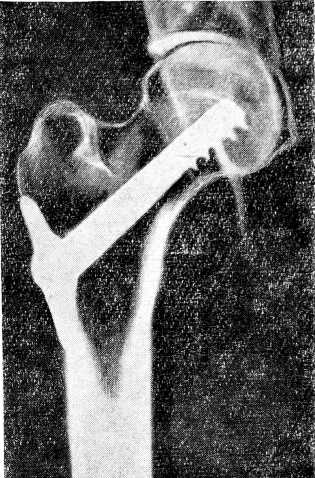

После повторной рентгенографии и убеждения в правильном расположении шурупа, легкими ударами вводятся лопасти (рис. 2), и торцовым ключом завинчивается стягивающий болт со сферической шайбой. На рис. 3 представлена схема верхнего эпифиза бедра с введенными фиксирующим штифтом и его частями.

Рис.3

На рис. 4 представлена рентгенограмма после введения штифта.